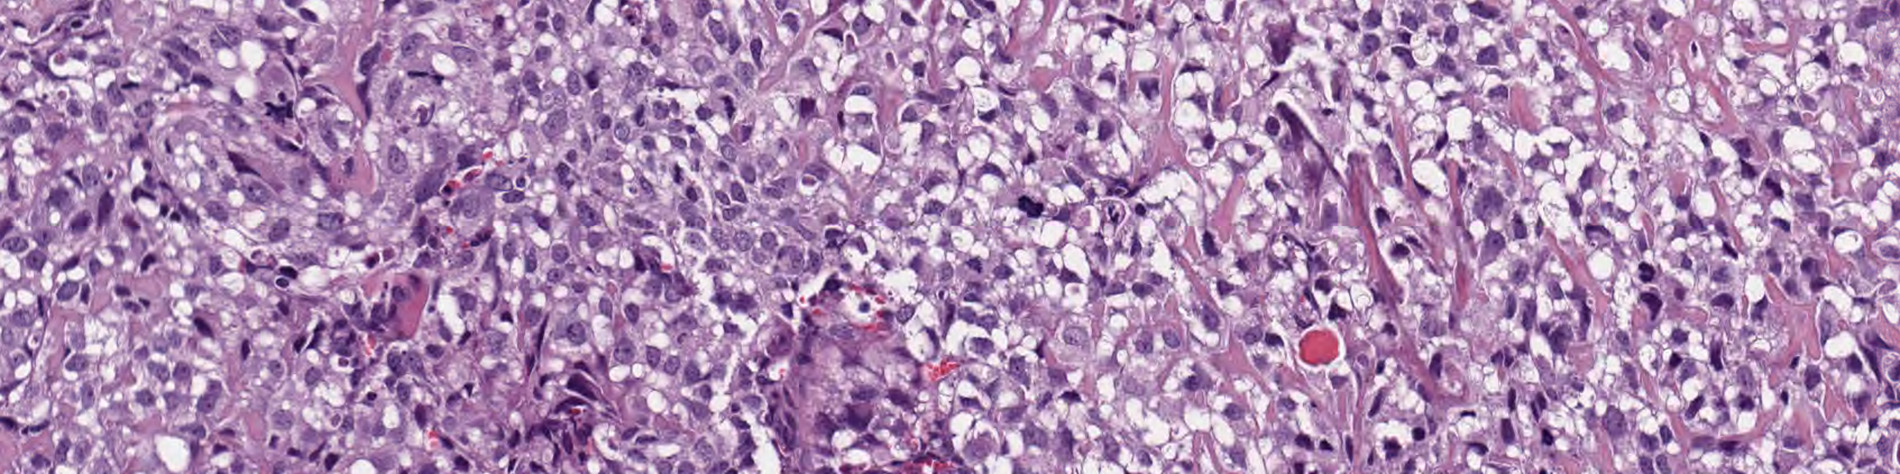

With the consent of patients and parents, researchers developed a system to grow St. Jude patient tumors in the same organ in mice. Such tumors are called orthotopic patient-derived xenografts. The standard approach has been to grow patient tumors in the flank of mice.

A comprehensive analysis comparing the original patient tumor to the orthotopic xenografts showed many orthotopic patient-derived xenografts retained their “molecular fingerprint” even after being grown in successive generations of mice. That suggests the tumors maintain their molecular identity when grown in the same microenvironment in mice and provide more accurate models for tracking tumor development and drug sensitivity, Dyer said.

Along with whole-genome and whole-exome sequencing and gene-expression profiling, the analysis included the most detailed examination yet of the genomic or clonal complexity of pediatric solid tumor orthotopic xenografts. Solid tumors include subsets of cancer cells called clones that have different mutations. Understanding and addressing clonal diversity is key to obtaining better cure rates because failure to kill all the clones in a tumor leaves the door open for cells from one clone to multiply and trigger a fatal relapse.